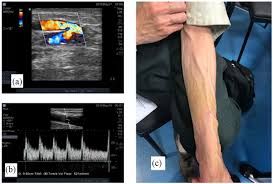

• সব ধরনের সাধারণ এবং স্পেশাল অর্গান ডুপ্লেক্স আলট্রাসনোগ্রাফি পরীক্ষা

• সকল ধরনের ভাস্কুলার অ্যাকসেস সার্জারি – কিডনি ডায়ালাইসিসের জন্য টেম্পোরারি ক্যাাথেটার, টানেল ক্যাথেটার এবং আর্টারিওভেনানাস ফিস্টুলা তৈরি করা

• ভেরিকোসিল ডায়াগনোসিস এবং তার চিকিৎসা